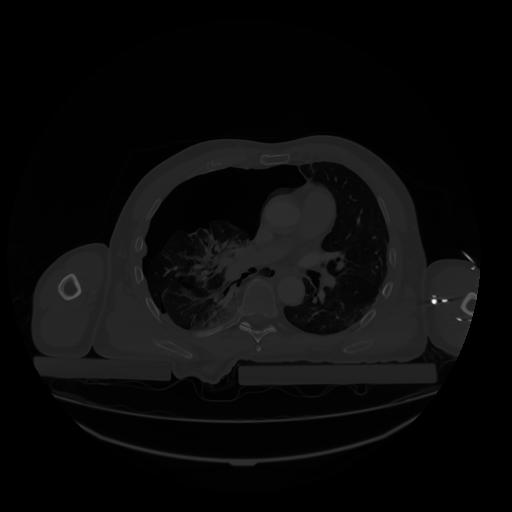

28 CUERPO,CE,Vol,2.0,CUERPO,,